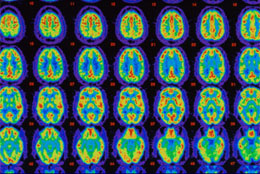

- Brain Tour Translated into 15 languages, this interactive tool provides a visual understanding of how a healthy brain works as well how Alzheimer's changes the brain. Alzheimer’s symptoms, such as behavioral and cognitive changes, are caused by damage to the brain.

Currently, Alzheimer’s is diagnosed mostly on the basis of neurological exams, but these exams cannot detect the disease until brain damage is extensive. A brain imaging method that can detect Alzheimer’s in its earliest stages provides the best opportunity to limit brain damage. To help further research to this end, the Alzheimer’s Association awarded a three-year grant to Abedelnasser Abulrob, Ph.D., and his colleagues at the University of Ottawa. These researchers who are investigating advanced ways to identify beta-amyloid in the brain, with the hope of detecting Alzheimer’s at its earliest stages.